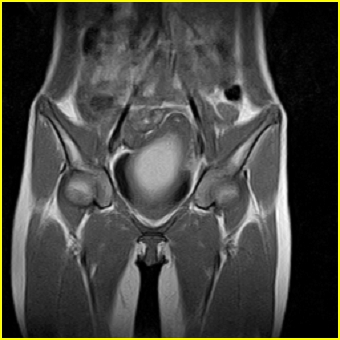

女、15岁、下腹疼痛2天,排尿困难1天。查体:处女膜闭锁,距处女膜约4至5cm处扪及一约5cm直径的圆形包块,张力较高,触痛明显、欠活动。b超提示子宫增大伴宫内增强回声团。

更正影像意见:阴道积血。

处女膜闭锁,阴道积血

处女膜闭锁,阴道积血,子宫积血.

处女膜闭锁,伴子宫及阴道积血.